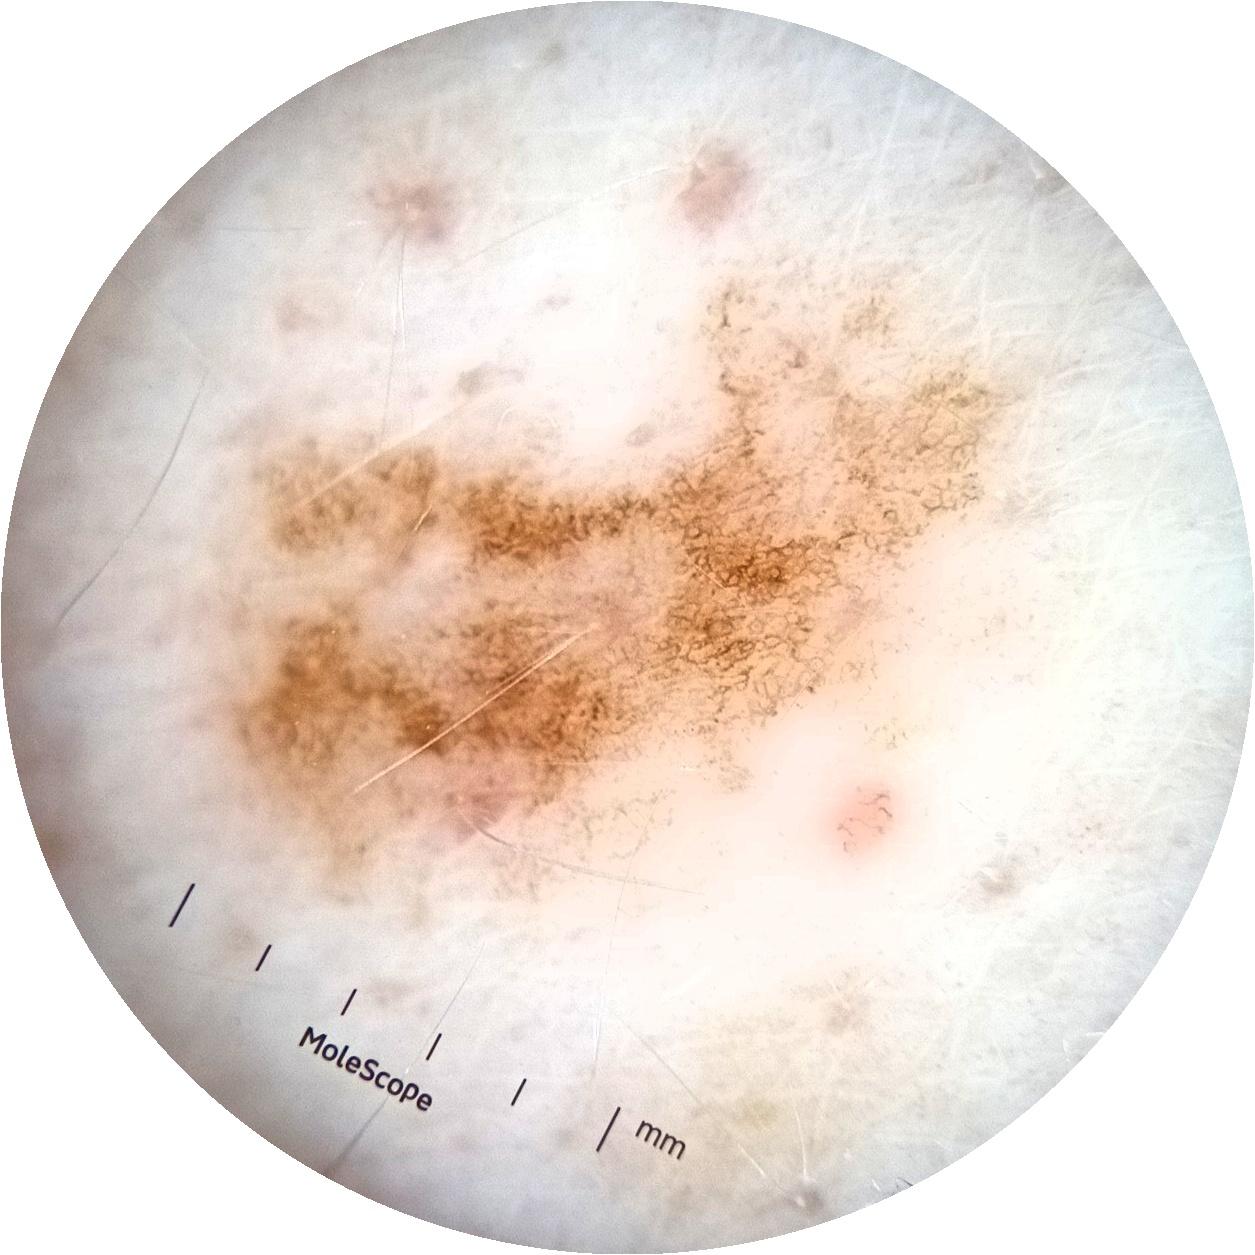

ISIC_3754278

MEL-SELF Trial, https://www.sydney.edu.au/medicine-health/our-research/research-centres/melself-project.html

acquisition_day 135

age_approx 65

anatom_site_1 Upper extremity

anatom_site_general upper extremity

diagnosis_1 Benign

diagnosis_confirm_type single image expert consensus

fitzpatrick_skin_type I

image_type dermoscopic